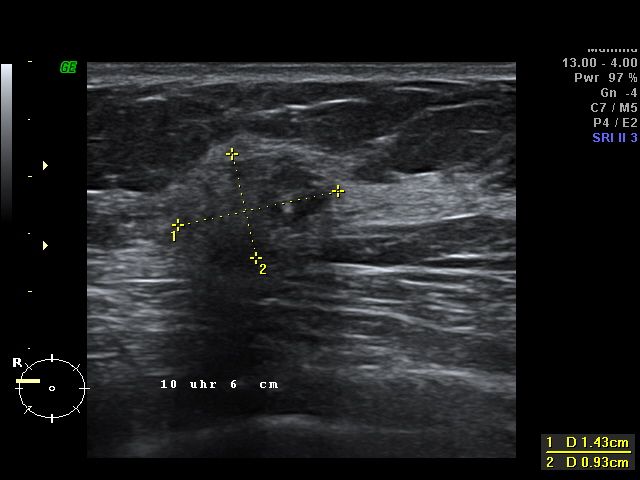

Neben den vorgeschriebenen Untersuchungen gibt es sinnvolle Ergänzungen wie z.B. Ultraschalluntersuchungen. Es ist ganz offensichtlich, dass Myome, Cysten und Brustbefunde durch die Ultraschalluntersuchung wesentlich früher entdeckt werden können als durch die Tastuntersuchung alleine.

Es wird dabei zusätzlich zur Kassen-Vorsorge eine Ultraschalluntersuchung der Brust und / oder eine Ultraschalluntersuchung von Gebärmutter und Eierstöcken durchgeführt. Diese Untersuchungen sind frei von belastenden Röntgenstrahlen und bietet eine deutlich bessere Früherkennung von Brustkrebs und Eierstockskrebs als die Tastuntersuchung alleine.